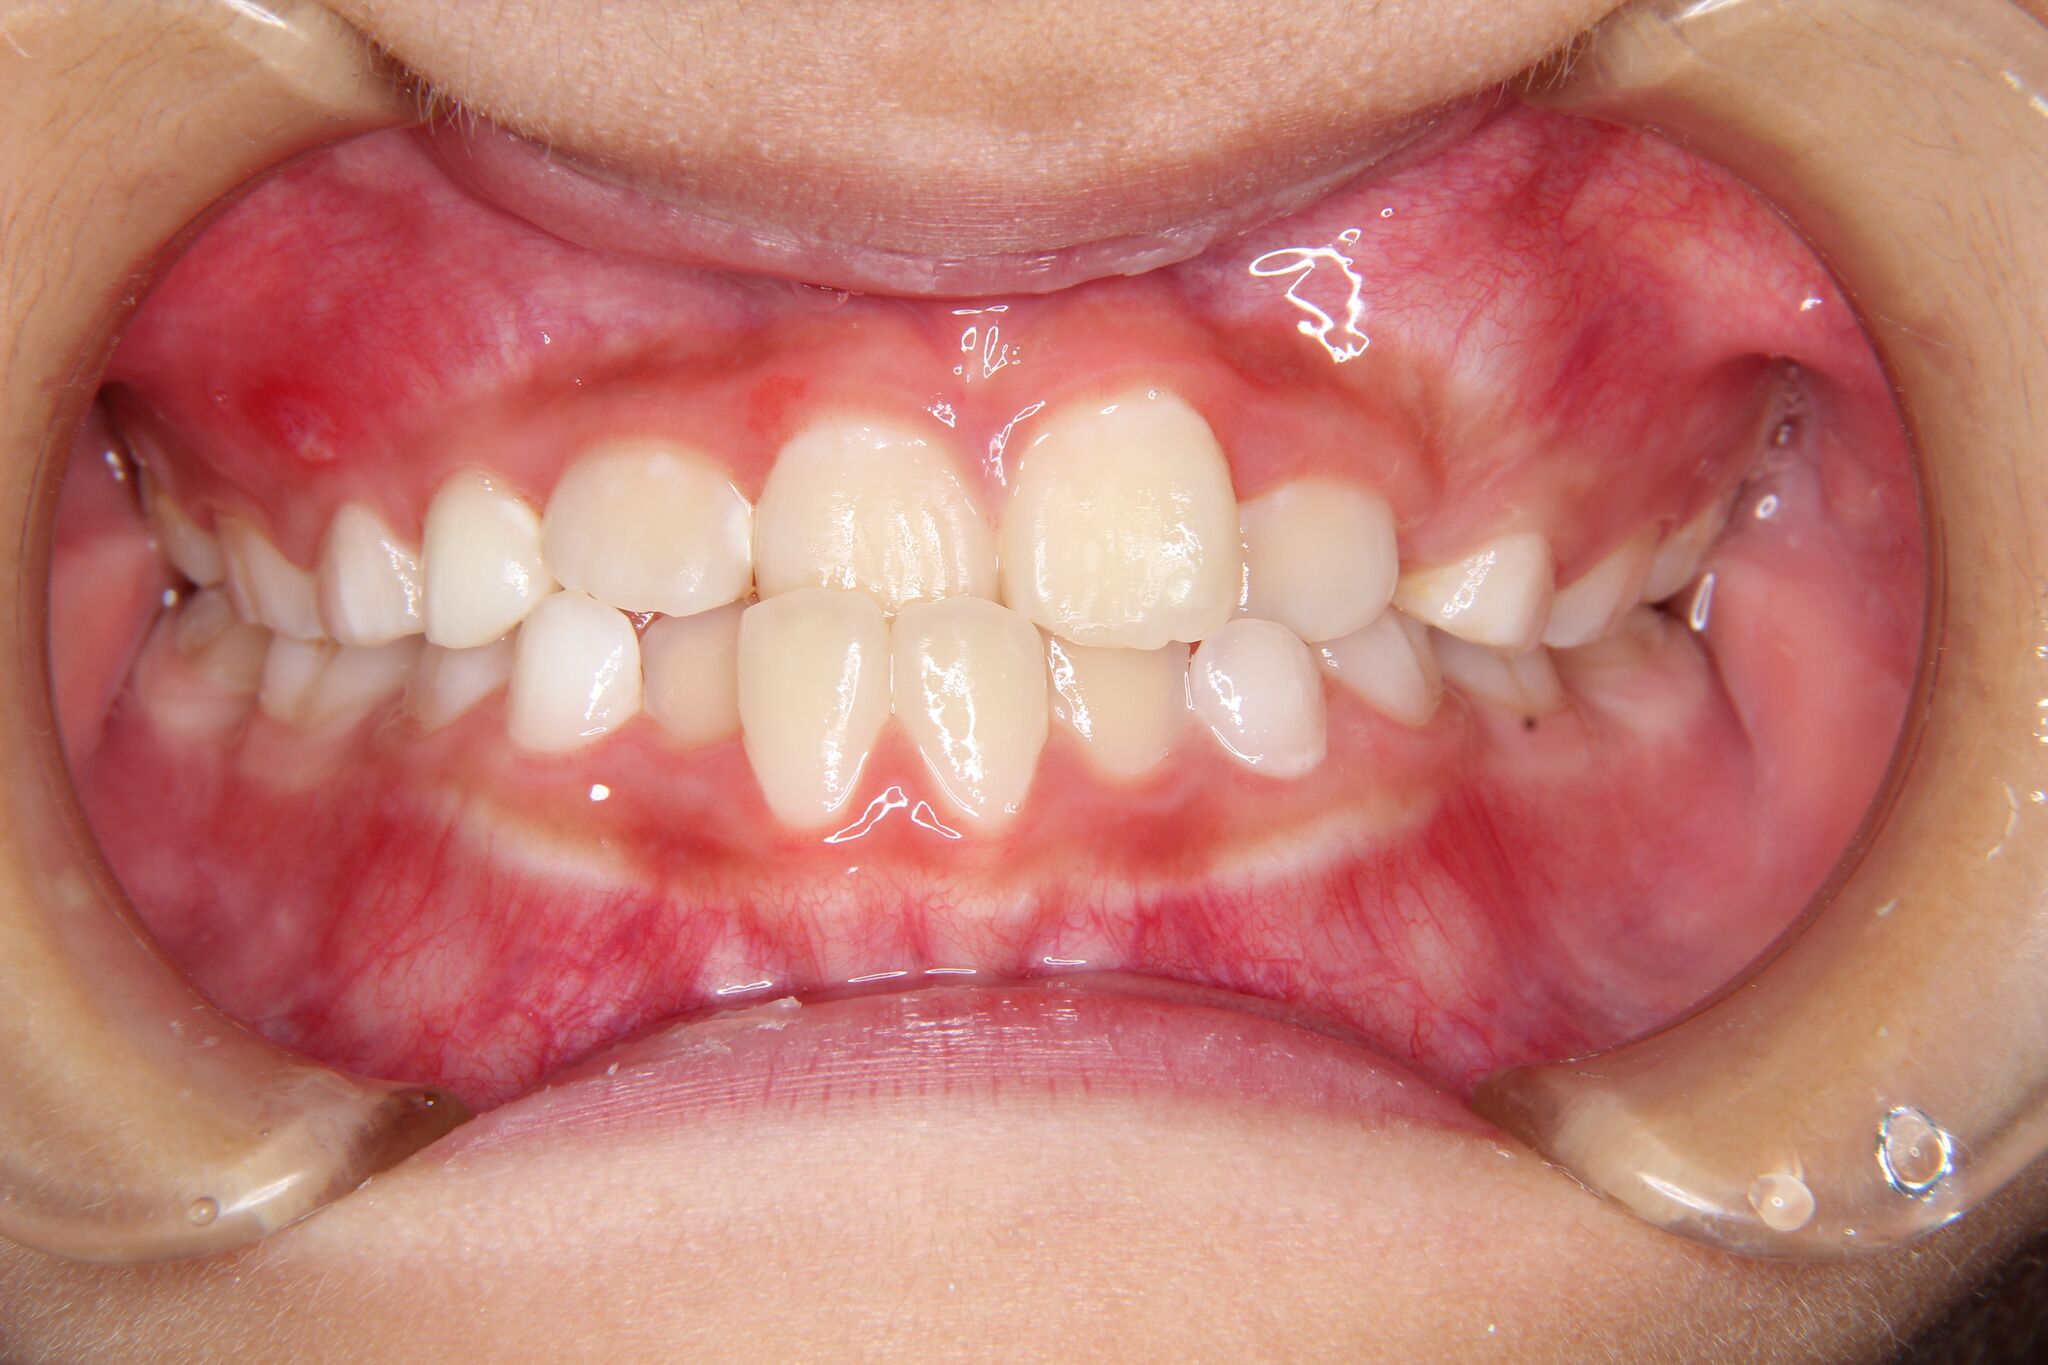

- 治療前 治療後

今回のケースは、

- 前歯が反対に噛んでいる

- 下顎が右にずれている

- 歯の叢生(がたがた歯)がある